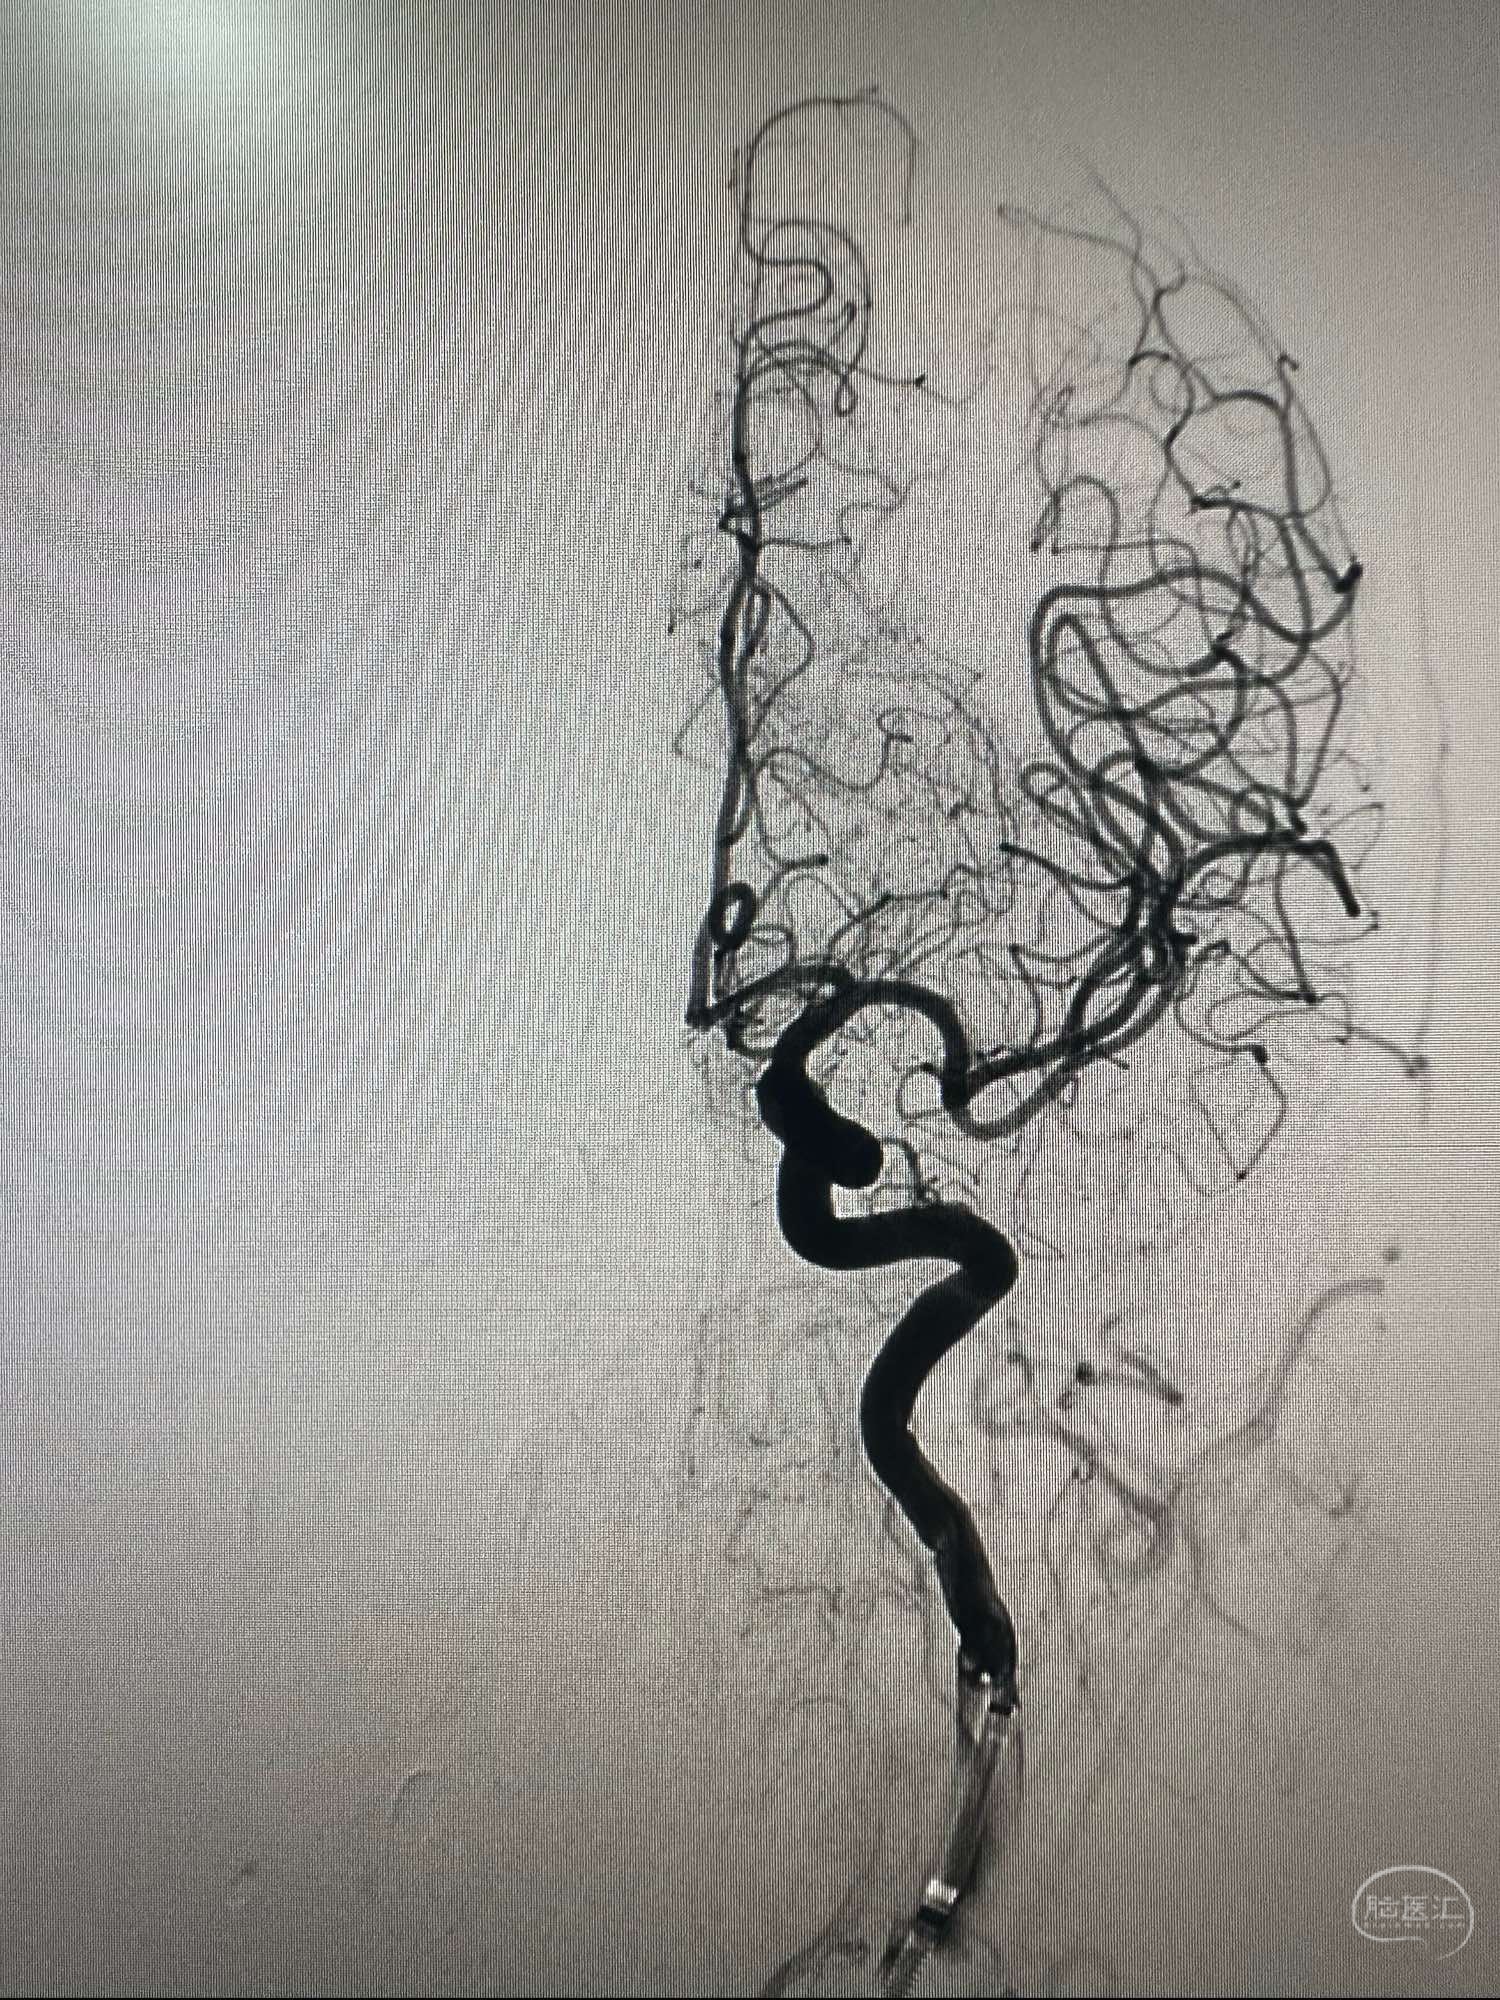

左侧